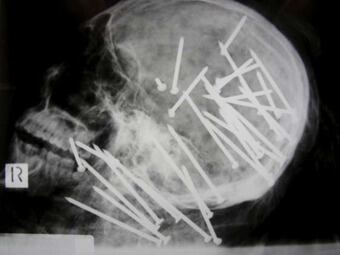

La policía australiana ha hecho pública estos días una impactante radiografía en la que puede verse el cráneo de un inmigrante chino, asesinado de 34 disparos en la cabeza y el cuello con una potente pistola de clavos